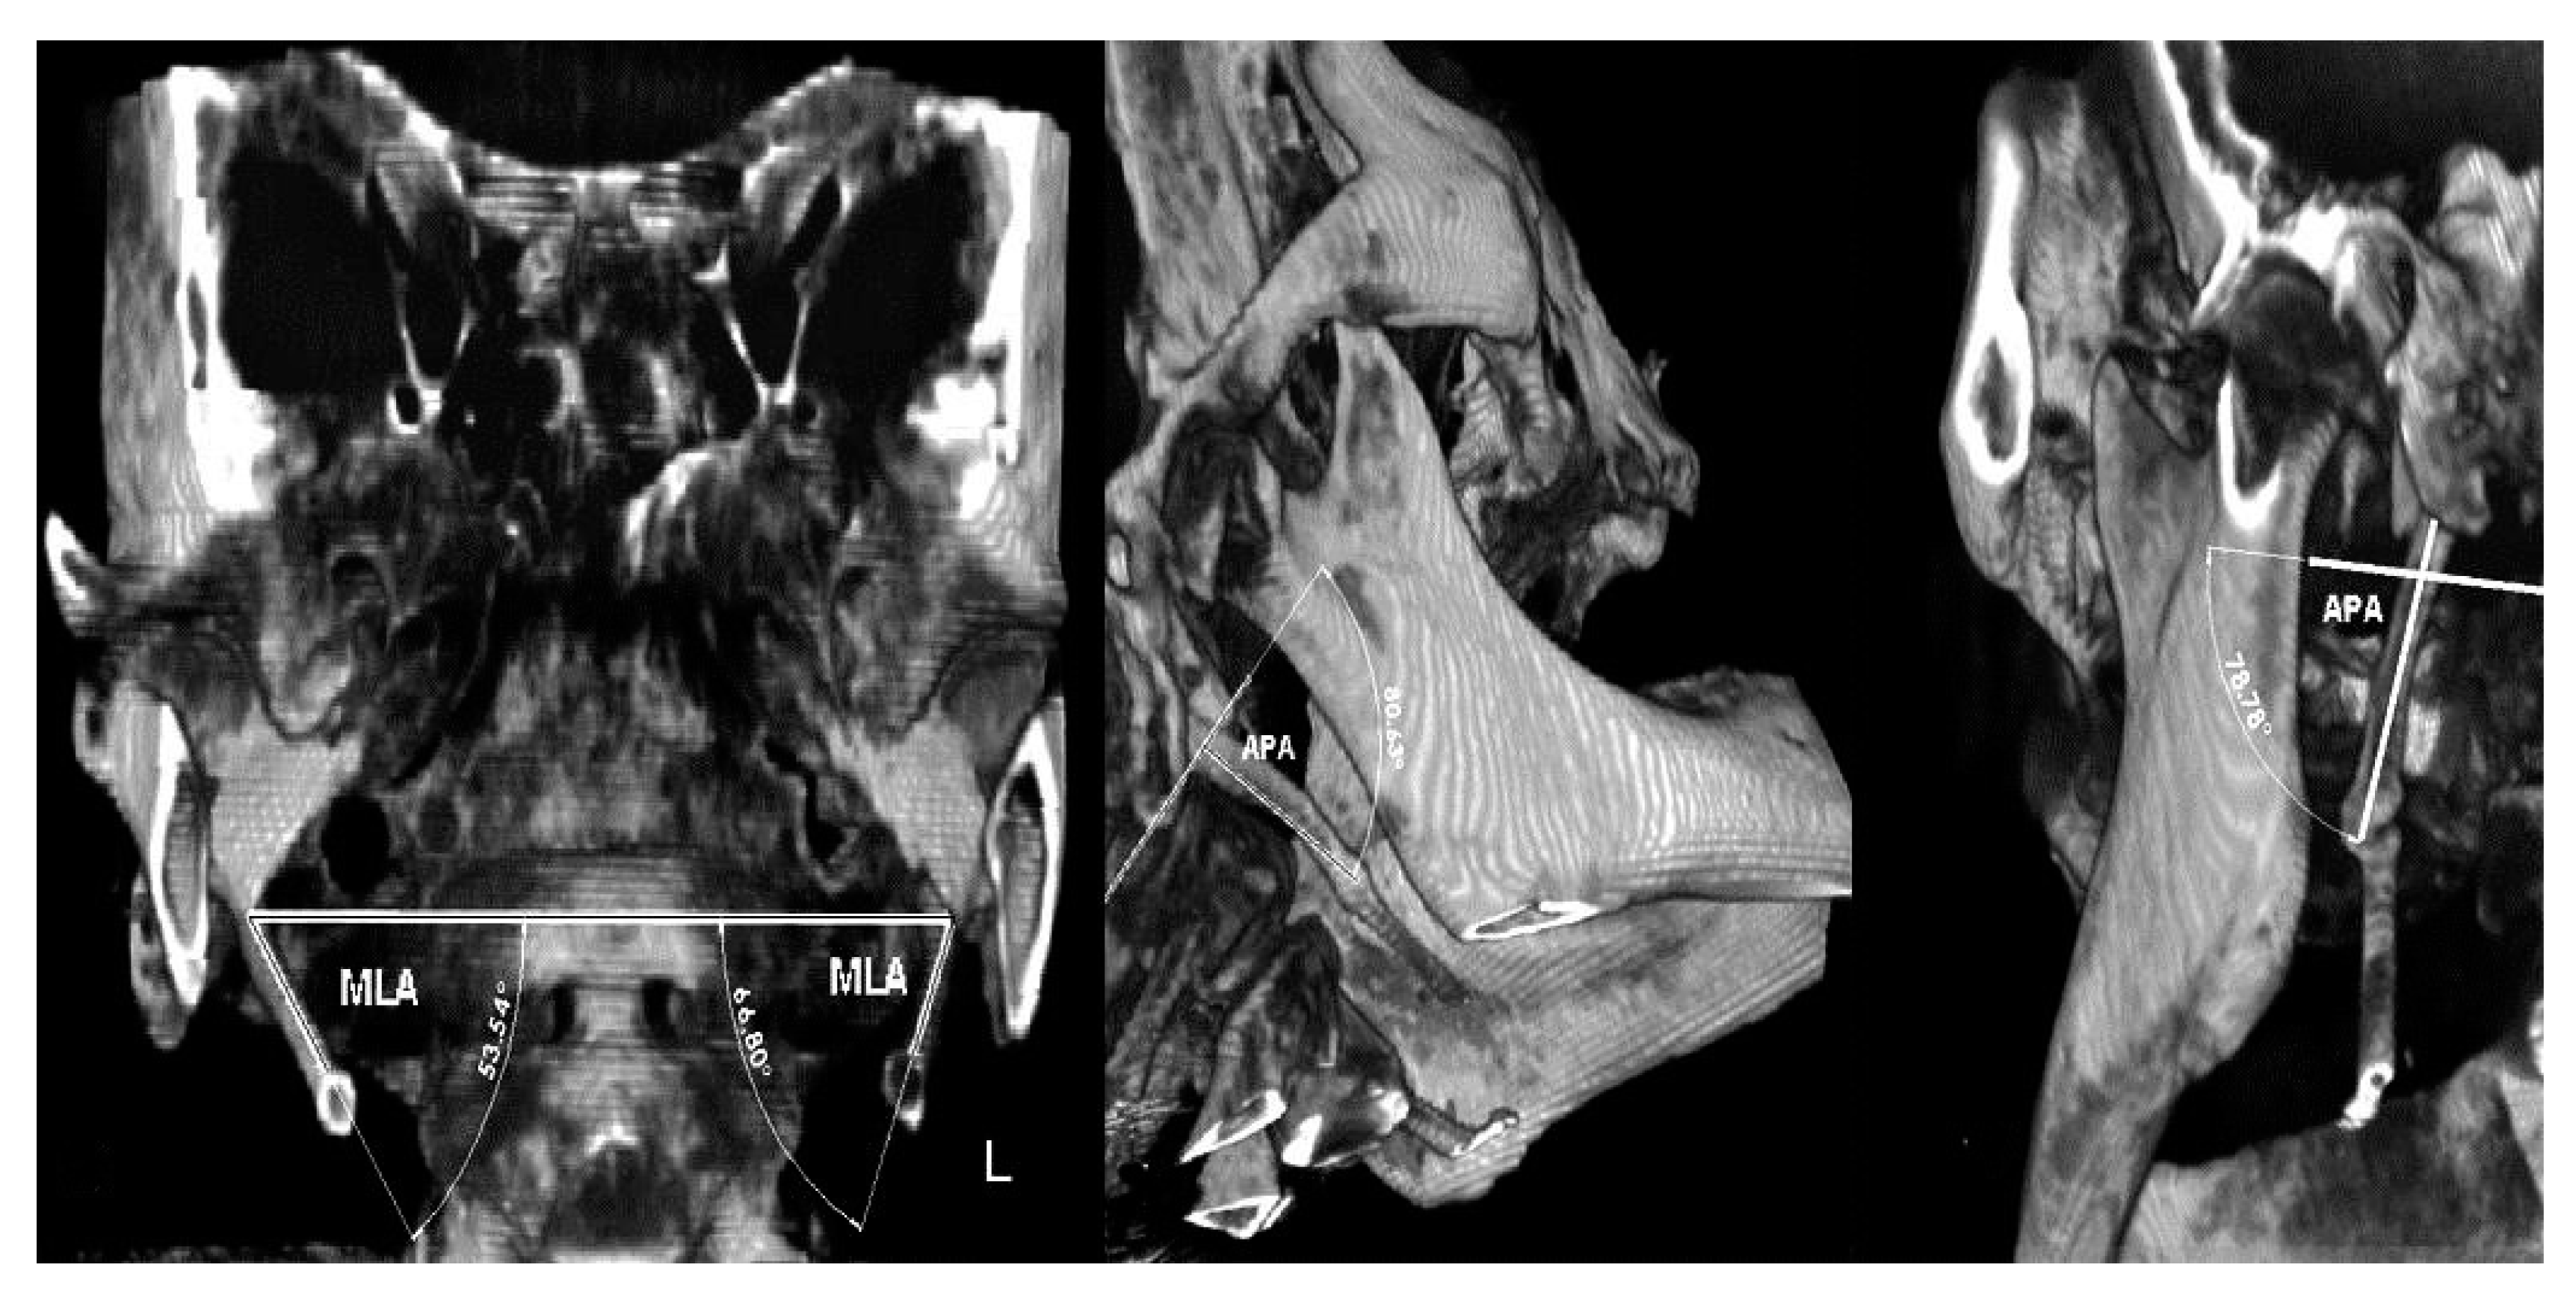

The extracted CBCT’s panoramic view shows an atypical bilateral elongation of the styloid process, with the unerupted impacted maxillary left canine and, on the right side, the sinus mucocele; the CBCT’s extracted panoramic and axial views of the maxilla shows a more detailed unerupted impacted maxillary left canine and two additional sinus pathologies in the maxillary sinuses; in the left maxillary sinus, there was chronic inflammatory hyperplastic mucosa, while the right maxillary sinus exhibited a sinus mucocele (Figure 4).

Figure 4. The axial cone beam computed tomography (CBCT) slice shows (upper image): panoramic radiography showing an unerupted maxillary left canine with a cyst-like formation around the canine crown and sinus pathology in the right maxillary sinuses. Elongated bilateral stylohyoid complex (SHC) processes are present and attain over one third of the mandibular ramus length (white arrows); (lower image): CBCT reconstruction images showing chronic inflammatory hyperplastic mucosa in the left maxillary sinus, impacted canine, while the right maxillary sinus exhibits a mucocele affecting the latero-basal portion of the sinus.